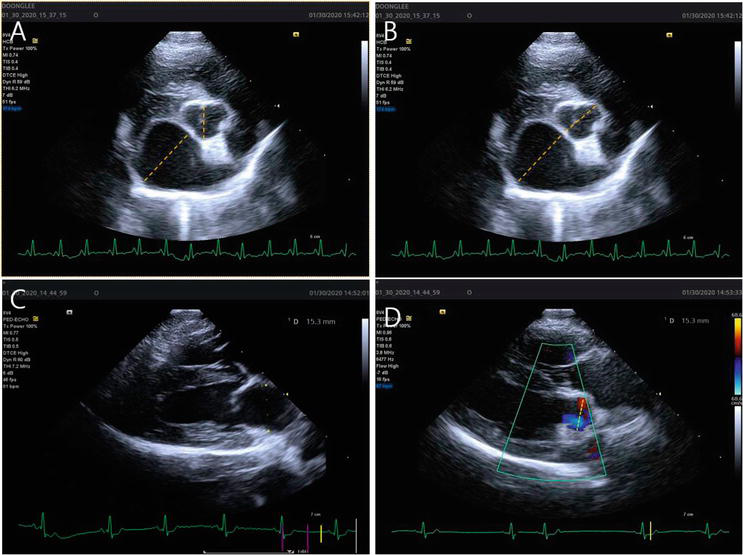

| LA:Ao Ratio | ≥1.6 | Right parasternal short-axis at AV level; early diastole |

Figure 3 - Echocardiographic LA:Ao measurement in right parasternal short-axis view. The method for measurement of left atrial to aortic root ratio (LA/Ao). (A) A LA/Ao obtained from a right parasternal short axis (LA/AoSx) by method 1 (see text). (B) A LA/Ao obtained from a right parasternal short axis (LA/AoSx) by method 2 (see text). (C and D) A LA/Ao obtained from a right parasternal long axis (LA/AoLx). For LA diameter (C), the measurement was made at end-systole 1 to 2 frames before the opening of the mitral valve leaflets. The measurement bisects the atrium extending from the mid-atrial septum in the near field to the bright pericardial echo of the LA lateral wall in the far field and is roughly parallel to the mitral annulus. For Ao diameter (D), the measurement of the aortic valve was made between the opened aortic valve leaflets in an early systolic frame when the Ao diameter is the greatest.

Reference: https://www.intechopen.com/chapters/71522 DOI: 10.5772/intechopen.91819